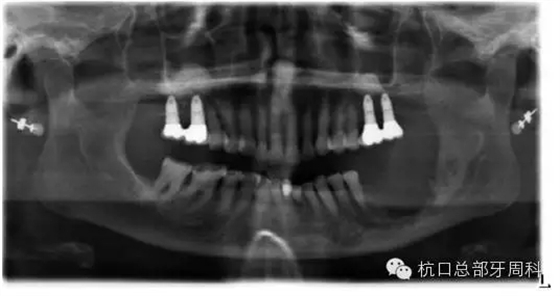

2012.4

2013.1

2013.3